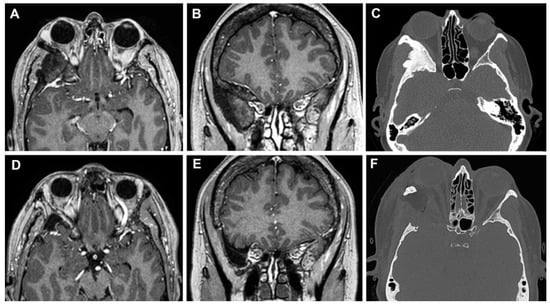

3.3.2. Case 2

3.3.3. Case 3